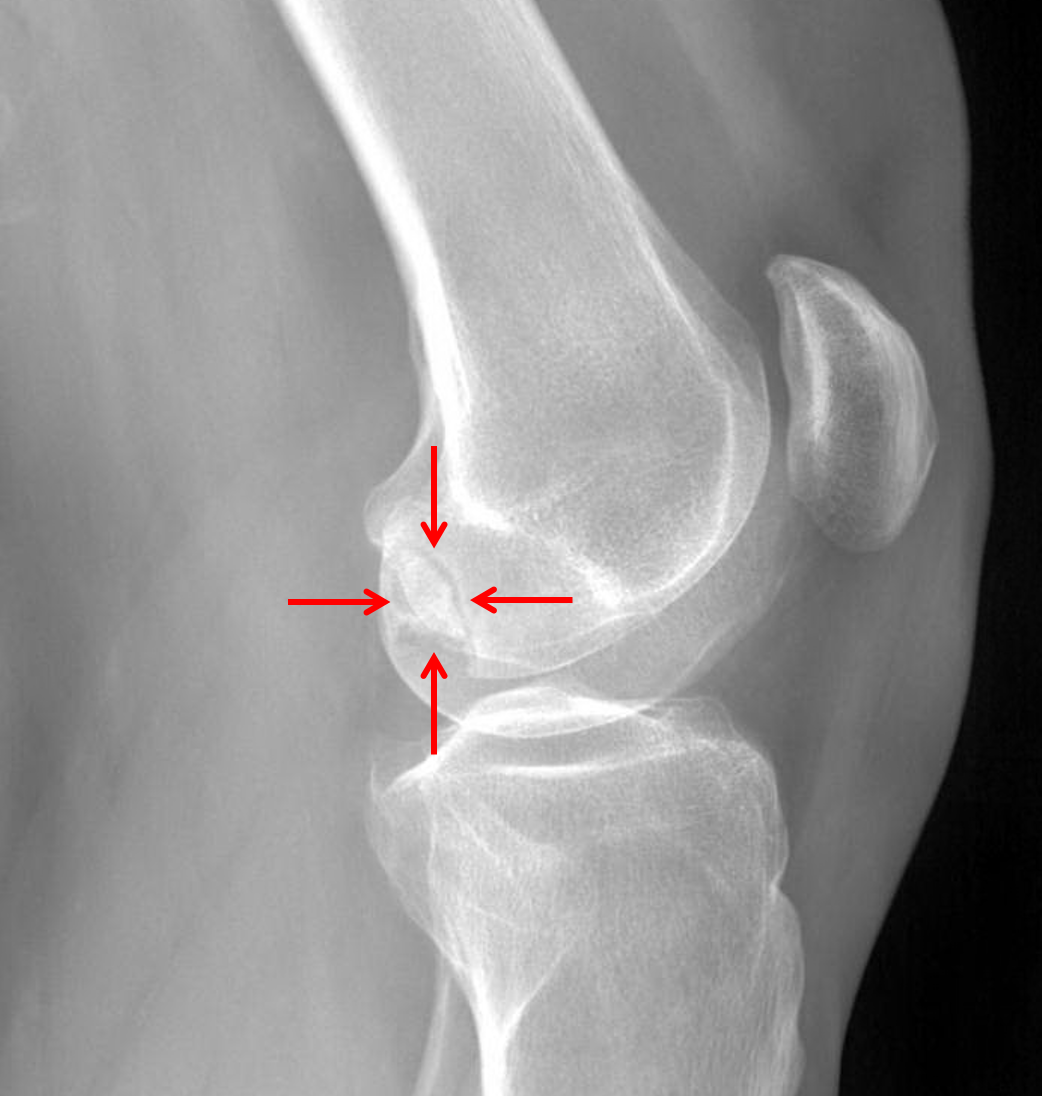

Subchondral insufficiency fracture was identified on medial femoral